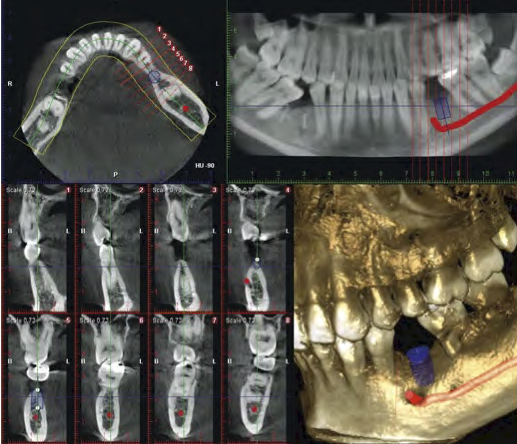

CTを利用した治療

今まで見えなかったことがわかる画像診断

従来のX線写真は二次元的な平面での診断しかできませんが、歯科用CTでは三次元の立体画像でのレベルに変わるので、より多くの情報が得られます。つまり、「見えなかったものが見える」「分からなかったことが分かる」、だから「治療の安全性が上がる」のです。